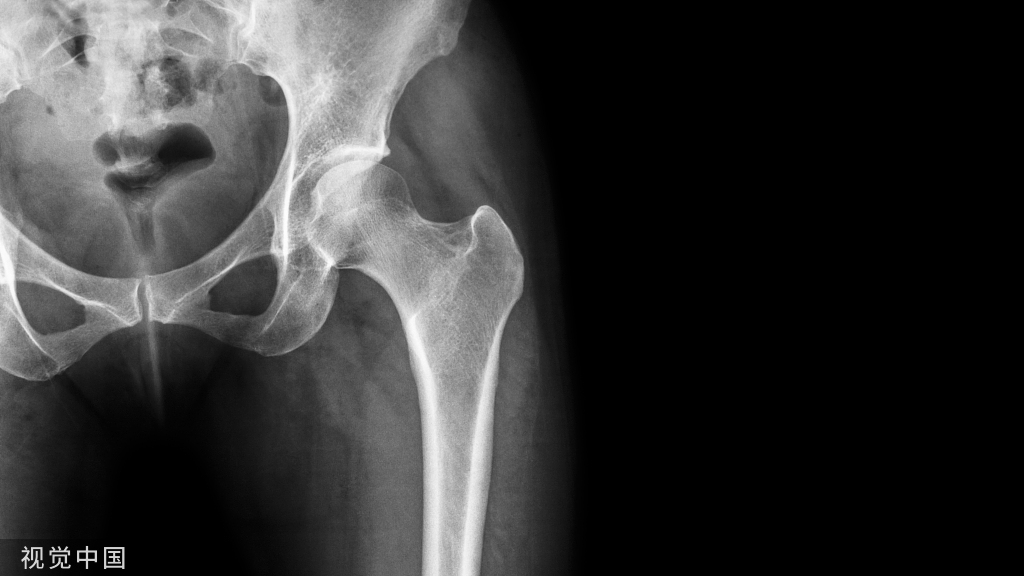

踝关节炎可以发生疼痛、关节不稳、活动度减少和功能障碍。最常见的踝关节炎是由创伤后引起,包括软组织损伤和韧带功能缺陷。目前,对于经保守治疗失败的踝关节进行性关节炎,踝关节融合术是金标准。